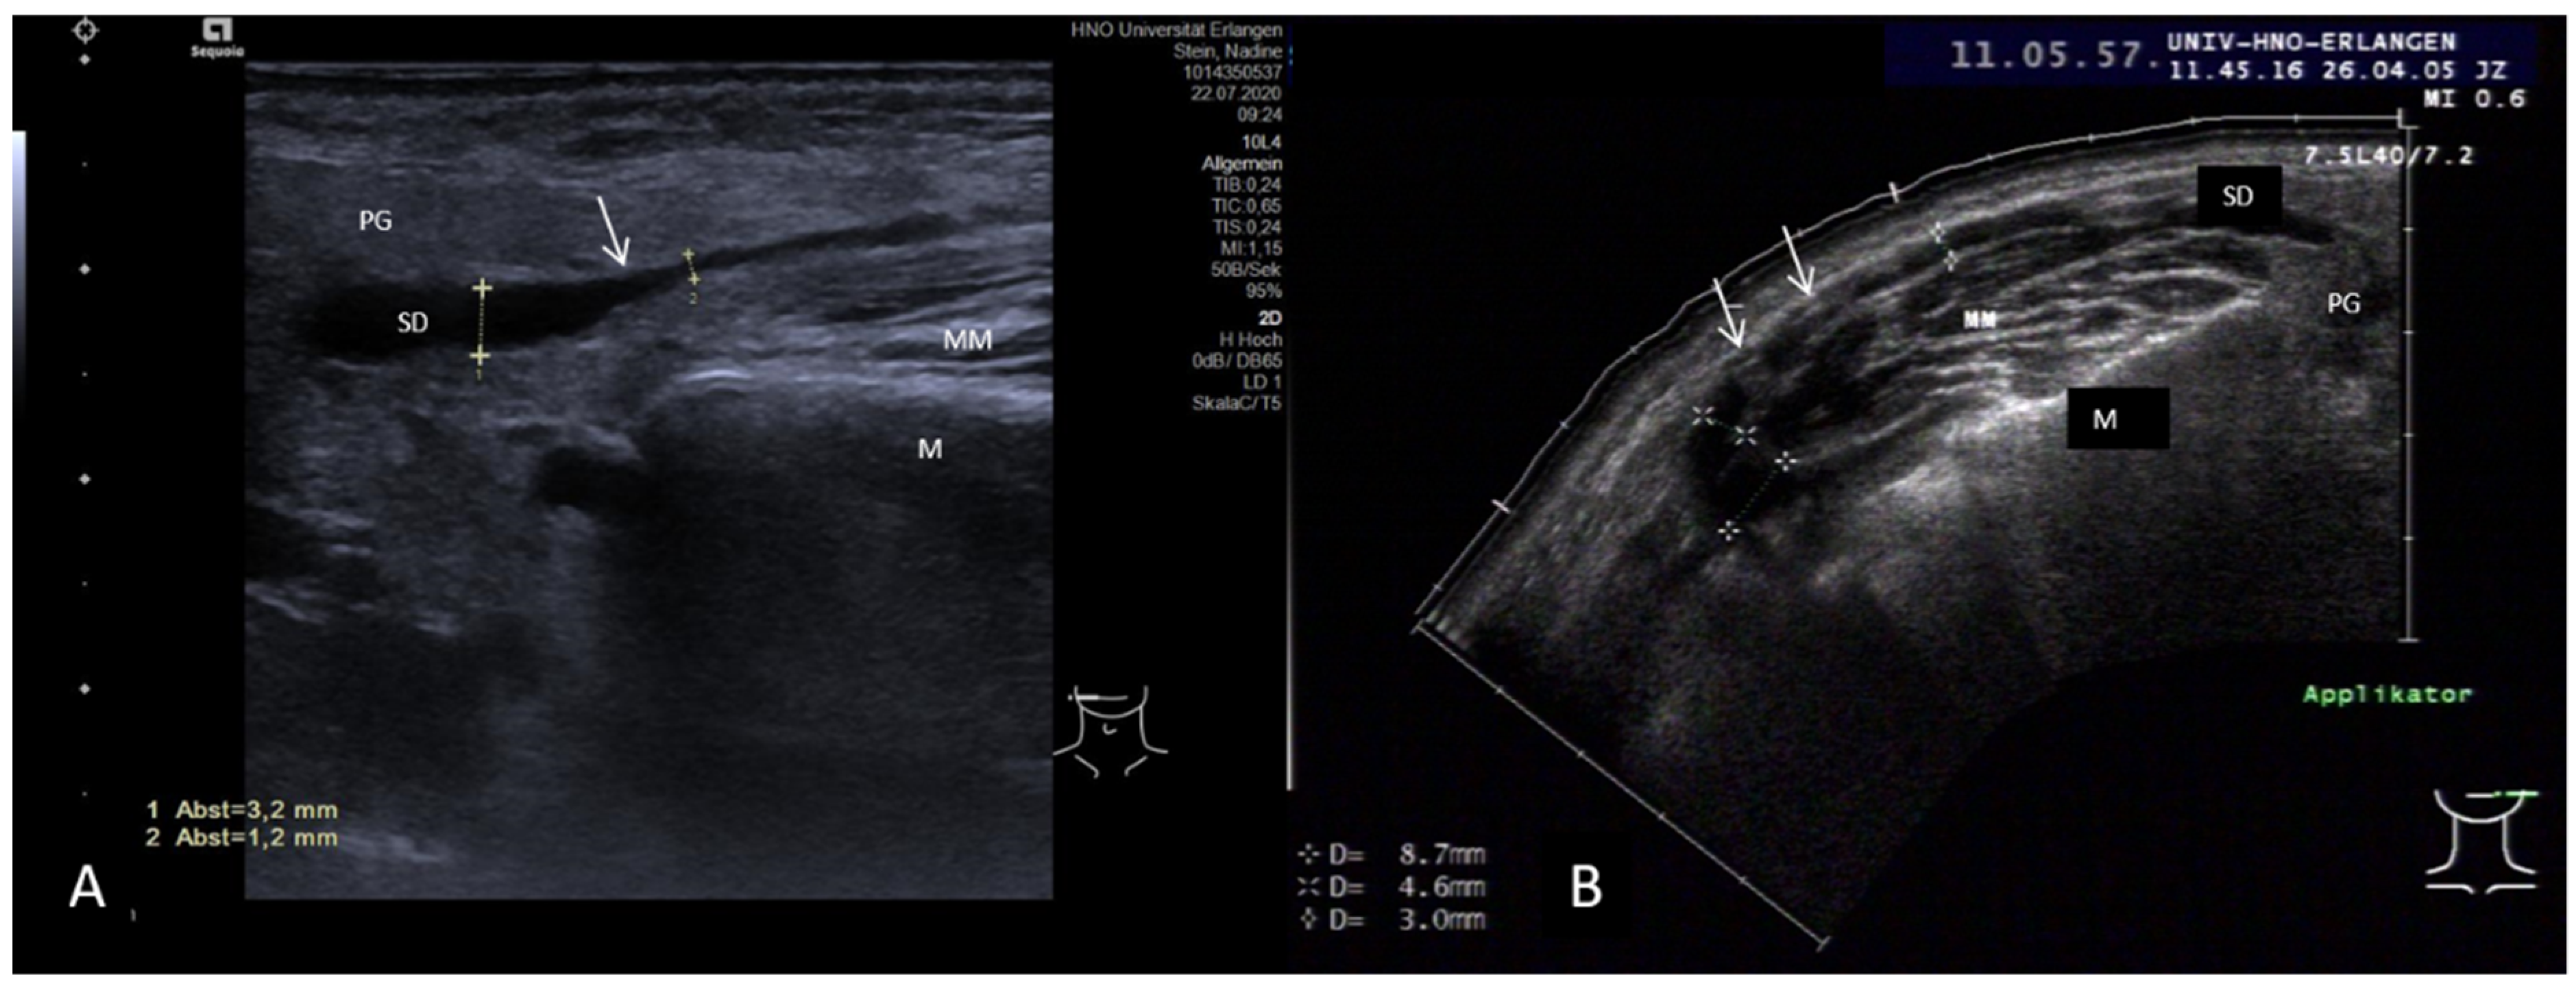

3.3.2. Obstructive Sialadenitis Caused by Sialolithiasis

3.3.3. Non-Sialolithiasis-Caused Unspecific Sialadenitis with Sialodochitis and/or Duct Stenosis with Primary or Secondary Obstruction